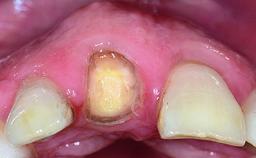

A healthy 28-year-old female patient presented for a consultation on treatment options to restore her upper right central incisor. At the clinical examination, the tooth responded to percussion and palpation. The gingiva was red and slightly swollen, with a mid-facial probing depth of 10 mm. The upper right lateral incisor showed no signs or symptoms, did not respond to exploration and percussion, and the vitality test was positive. The periapical radiograph revealed that tooth 11 had been endodontically treated, with no lesion evident at the apex. A small radiopaque calcified structure surrounded by a narrow radiolucent zone (3 × 3 mm) was present at the apex of tooth 12.